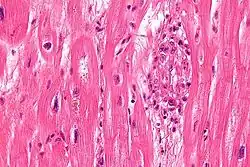

S. pyogenes has a cell wall composed of branched polymers which sometimes contain M protein, a virulence factor that is highly antigenic. The antibodies which the immune system generates against the M protein may cross-react with heart muscle cell protein myosin,[15] heart muscle glycogen and smooth muscle cells of arteries, inducing cytokine release and tissue destruction. However, the only proven cross-reaction is with perivascular connective tissue. This inflammation occurs through direct attachment of complement and Fc receptor-mediated recruitment of neutrophils and macrophages. Characteristic Aschoff bodies, composed of swollen eosinophilic collagen surrounded by lymphocytes and macrophages, can be seen on light microscopy. The larger macrophages may become Anitschkow cells or Aschoff giant cells. Rheumatic valvular lesions may also involve a cell-mediated immunity reaction as these lesions predominantly contain T-helper cells and macrophages.[16]

In rheumatic fever, these lesions can be found in any layer of the heart, causing different types of carditis. The inflammation may cause a serofibrinous pericardial exudate described as "bread-and-butter" pericarditis, which usually resolves without sequelae. Involvement of the endocardium typically results in fibrinoid necrosis and wart formation along the lines of closure of the left-sided heart valves. Warty projections arise from the deposition, while subendocardial lesions may induce irregular thickenings called MacCallum plaques.